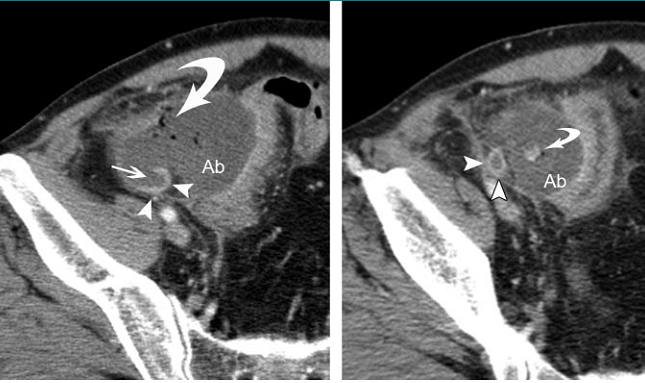

4. 阑尾周围脓肿

阑尾壁不连续(特异度100%)--增强扫描

阑尾腔内粪石或对比剂外漏(特异度100%)

阑尾周围游离气体(特异度99~100%)

蜂窝织炎(特异度95~96%)

脓肿形成(特异度98~100%)